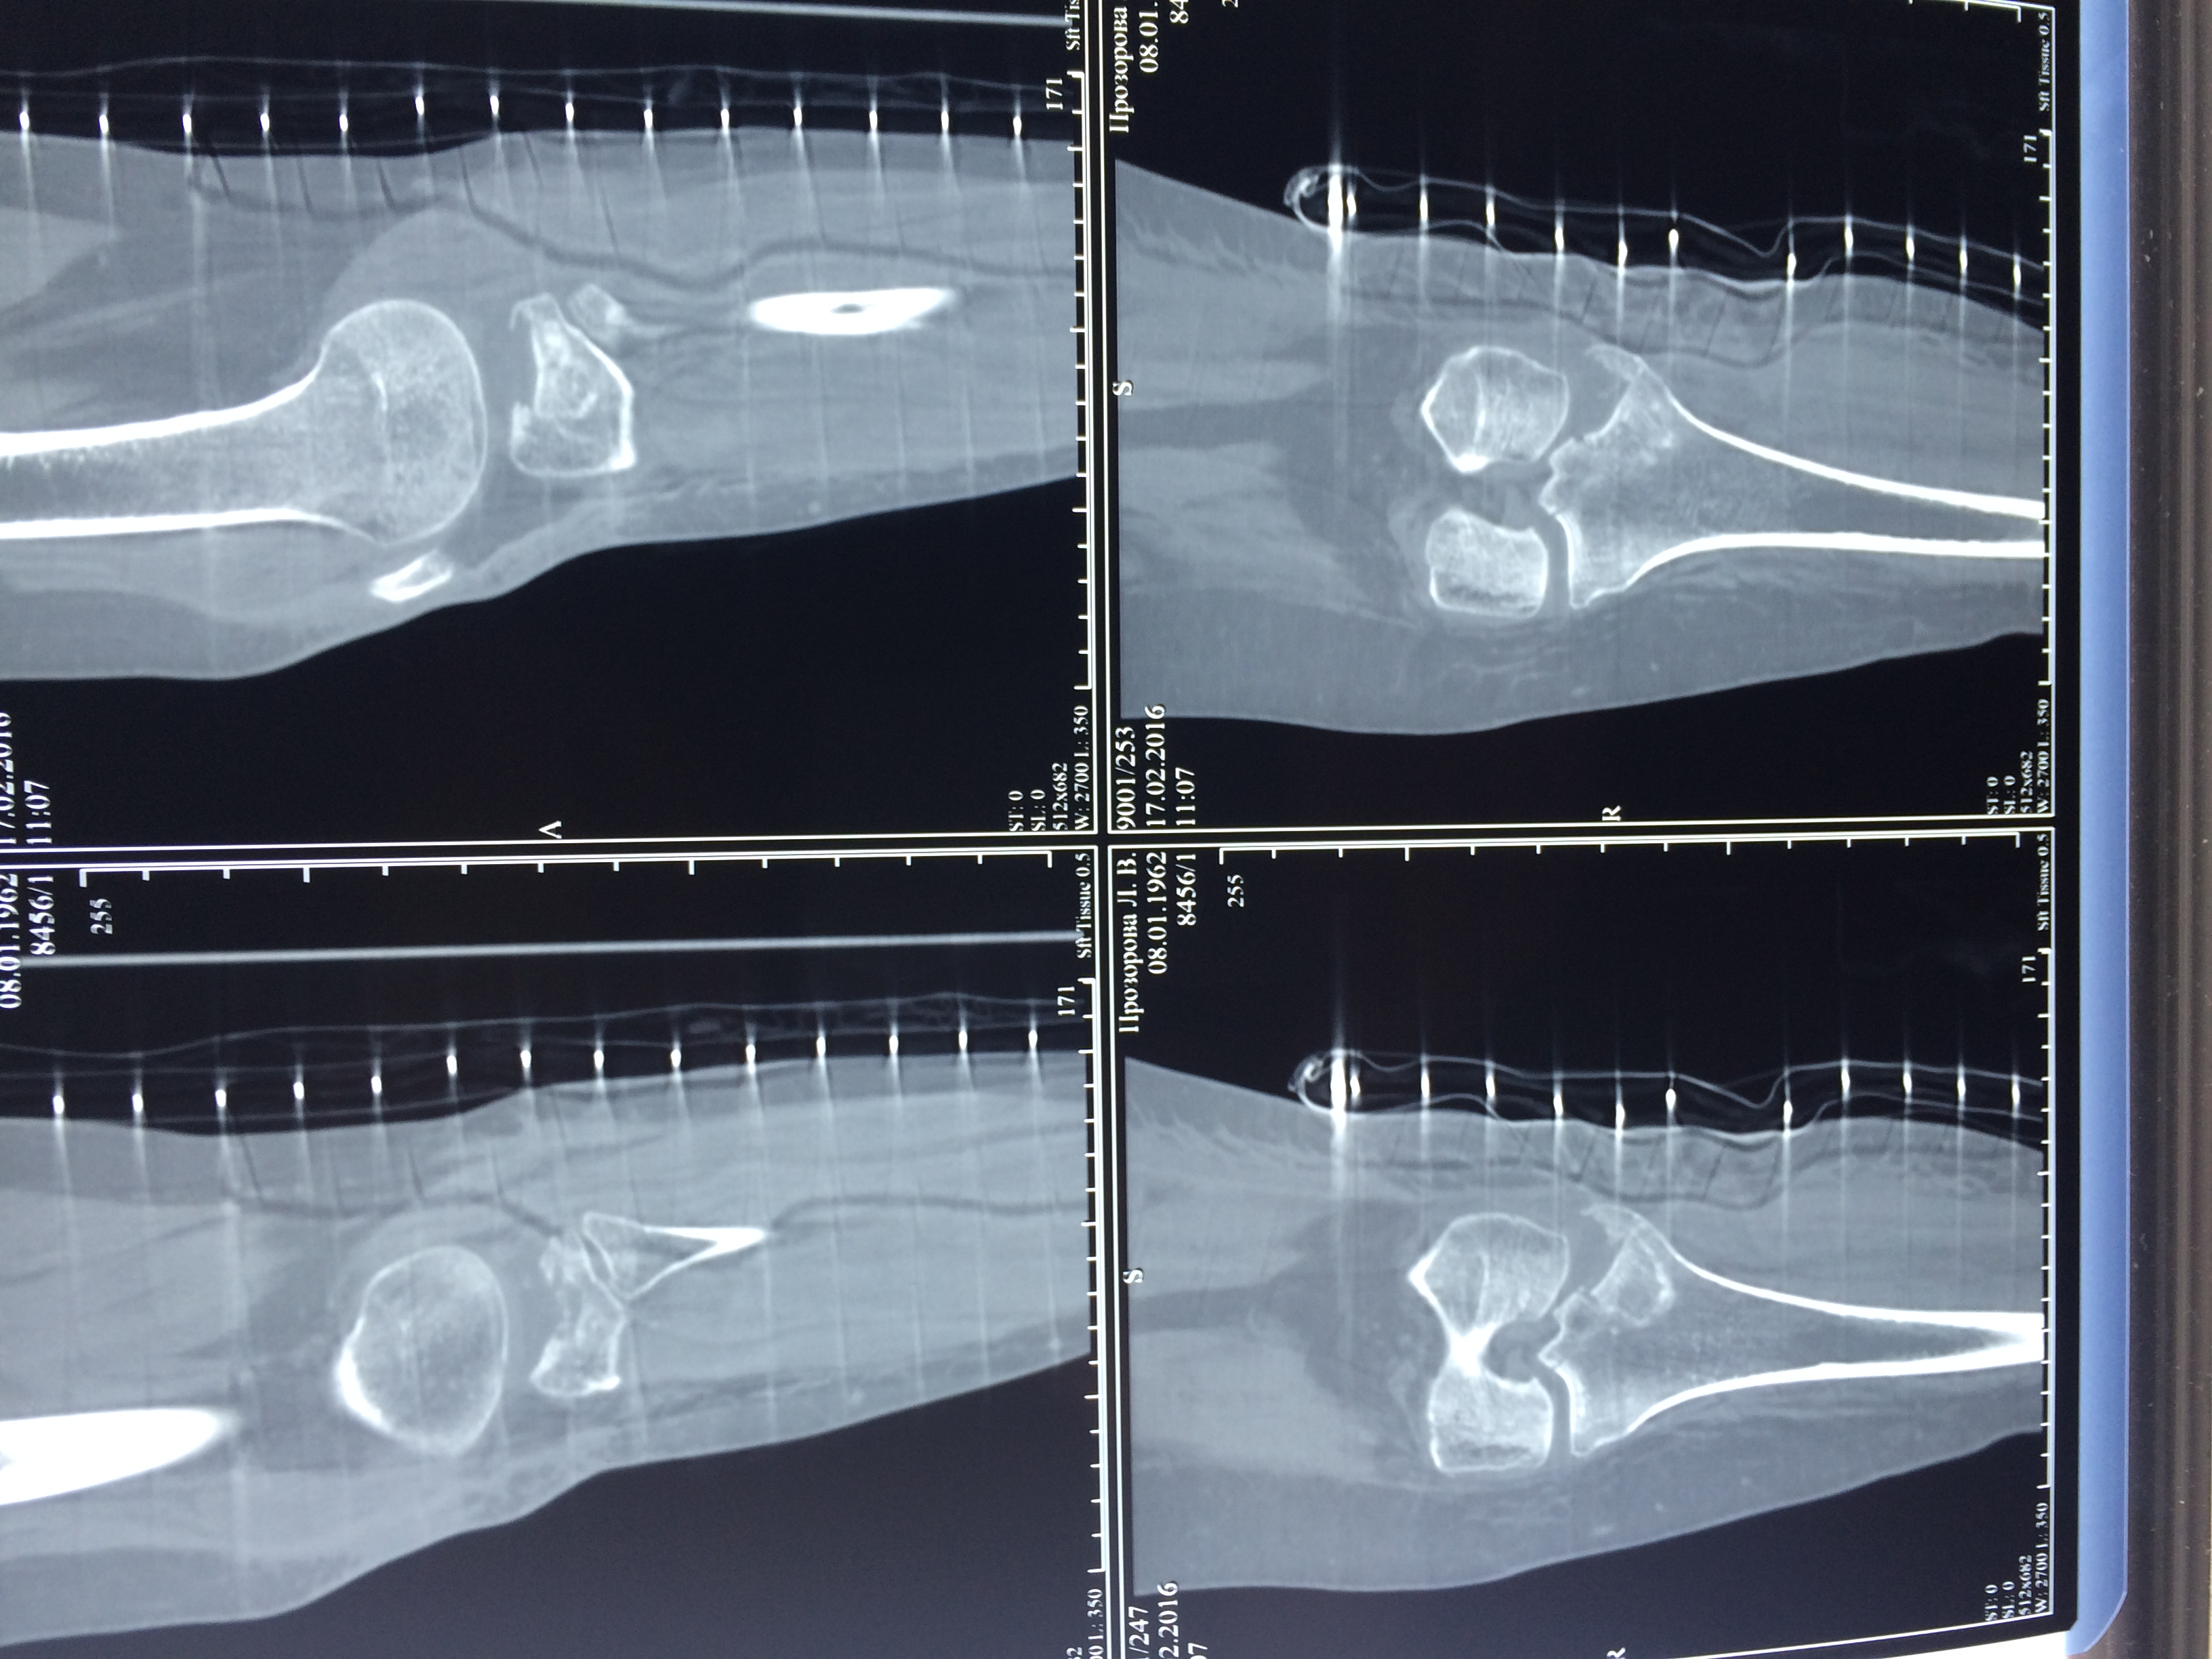

Использование материала Остеоматрикс при импрессионном оскольчатом переломе наружного мыщелка большеберцовой кости по типу Schatzker II

Использование материала Остеоматрикс при импрессионном оскольчатом переломе наружного мыщелка большеберцовой кости по типу Schatzker II.